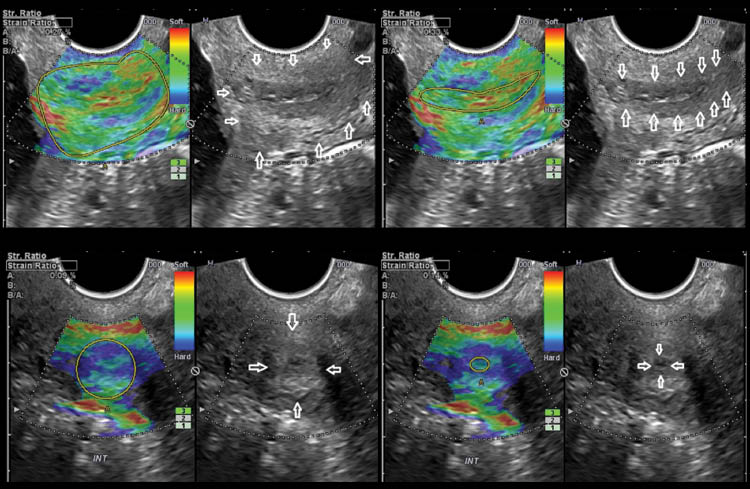

All patients were enrolled before 11 weeks of gestation when the first ultrasound was performed, and gestational age was consistent with the results of crown-rump length measurement. The cervix was evaluated at 16–24 weeks of gestation using transvaginal ultrasound (Hitachi 8–4 MHz, HI Vision 900; Hitachi Medical Corporation, Tokyo, Japan). Cervical length was measured in a sagittal view of the cervix with a clear image of the endocervical canal, the internal and external cervical os, and with a similar size of the anterior and posterior cervical lips [107]. For elastography quantification, three cervical projections were analyzed: mid-sagittal at the same level of the cervical length measurement, and two cross-sectional: one at the level of the internal os, and the other at the level of the external cervical os [62] (Figure 1). The proposed regions of interest were selected based on the feasibility of obtaining the ultrasound images and to delineate the regions of interest. The sagittal plane was the same used for cervical length measurement, and the two cross-sectional views were obtained with a 90° rotation of the ultrasound probe. Each plane was examined in two regions of interest (ROI), the endocervical canal and entire cervix, delineated as previously described [62].

Cervical elastography and strain rate calculation in sagittal and cross sectional projections of the cervix. The boundaries of the endocervical canal and of the entire cervix are highlighted in the corresponding gray scale image.